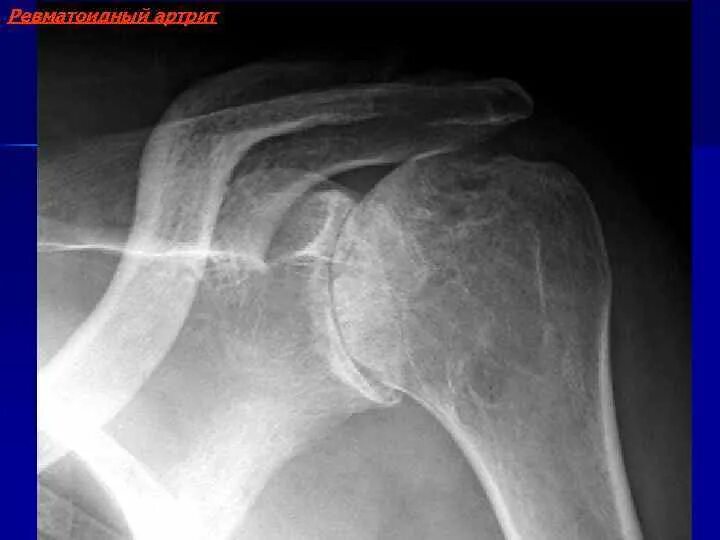

Как лечить артроз плечевого сустава 2 степени